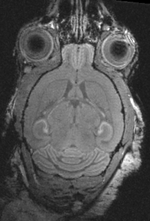

shown are, from left to right, panels of axial, sagittal and coronal views.

original brain in non-RAS orientation original, not RAS

original brain in proper RAS orientation original,after reorientation into RAS